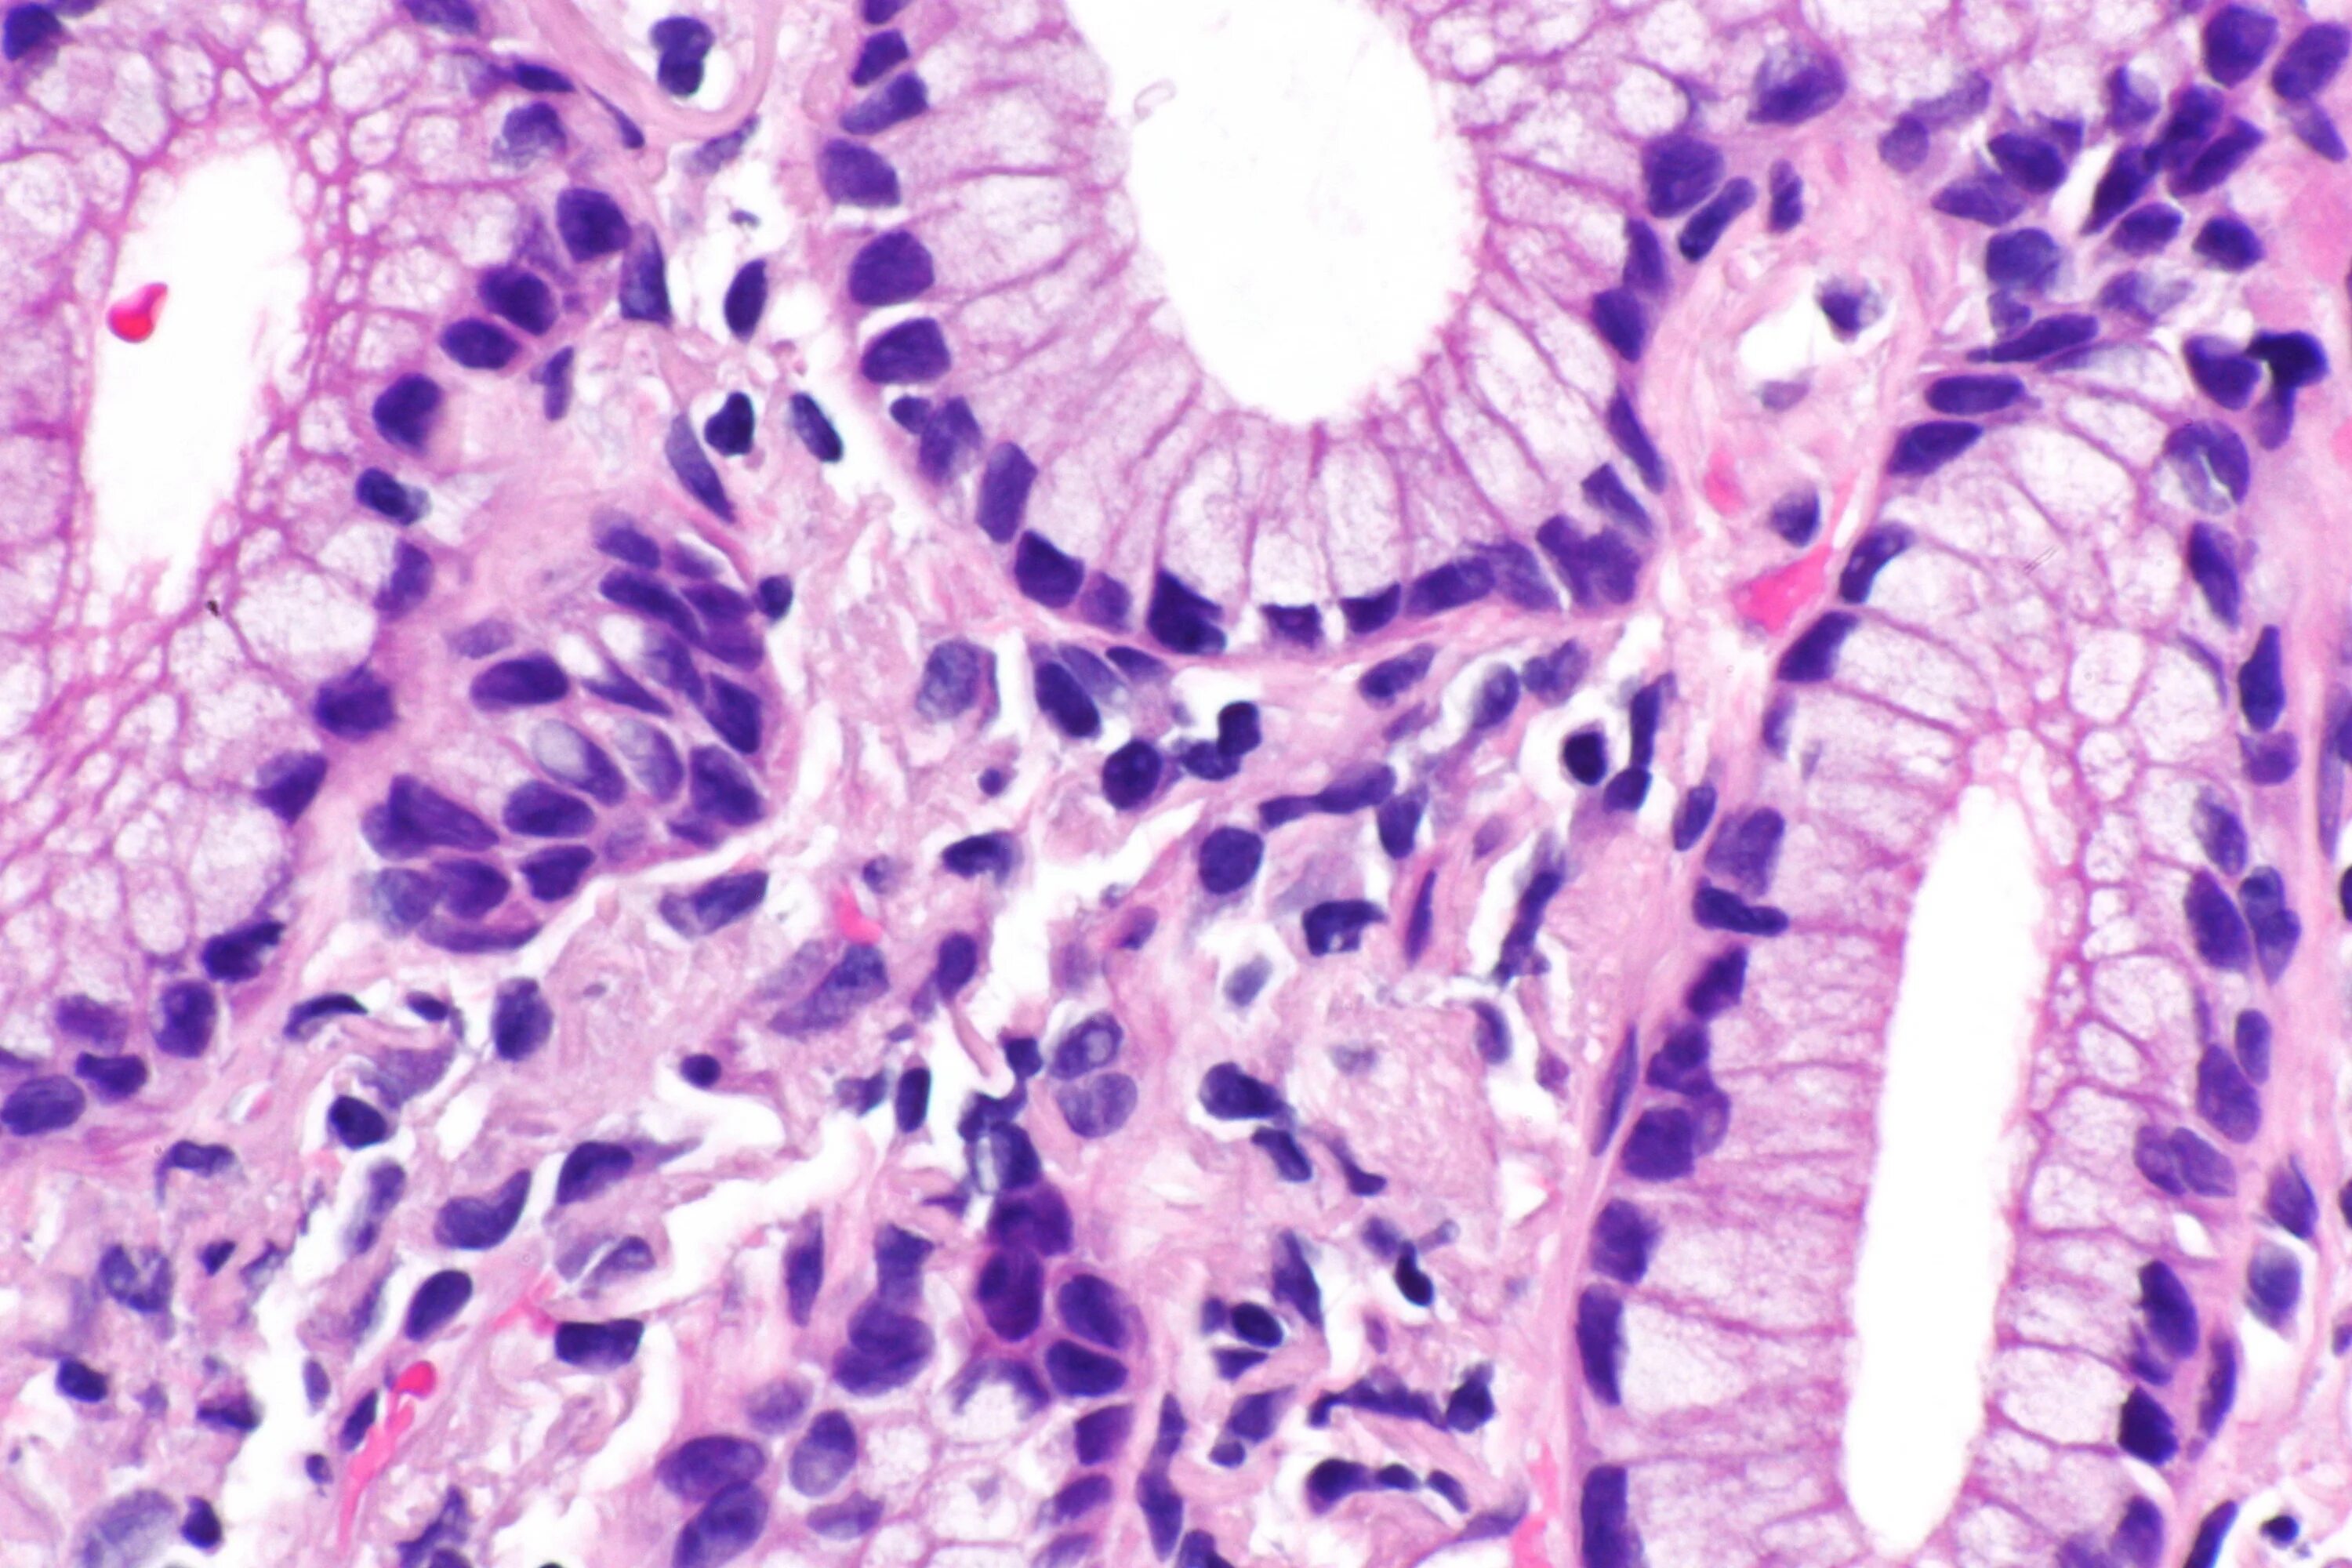

Гистологически аденокарцинома